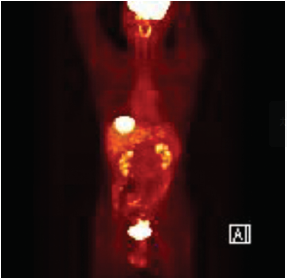

4. 양전자방출 단층촬영(PET) 및 PET-CT 검사

일반적으로 암세포가 정상세포에 비해 대사활동이 빠른 점을 이용하여 포도당에 양전자 방출체를 표지물질로 부착시켜 주사한 후 표지물질로부터 방출되는 감마선으로 암세포를 발견하는 검사법입니다. 그러나 이 검사로부터 얻어지는 영상은 암의 정확한 위치가 어디인지 구별하기 어려울 때도 있고 암이 아닌 염증성 변화에도 양성을 보이는 단점이 있습니다. 이러한 단점을 보완하기 위해 PET검사와 함께 CT검사도 시행하여 두 검사의 결과를 하나의 영상으로 조합하는 PET-CT검사가 새로이 개발되었습니다. 이 검사는 단독으로 시행되는 일은 드물며 수술 전 CT에서 간전이 등이 의심될 때 MRI검사와 함께 간 내의 전이암 개수의 정확한 파악이나 타 장기로의 전이를 확인하고자 할 때 사용되기도 하고 특히 수술 후 추적 CT검사에서 재발 또는 전이가 의심되는 경우에 추가로 사용됩니다.